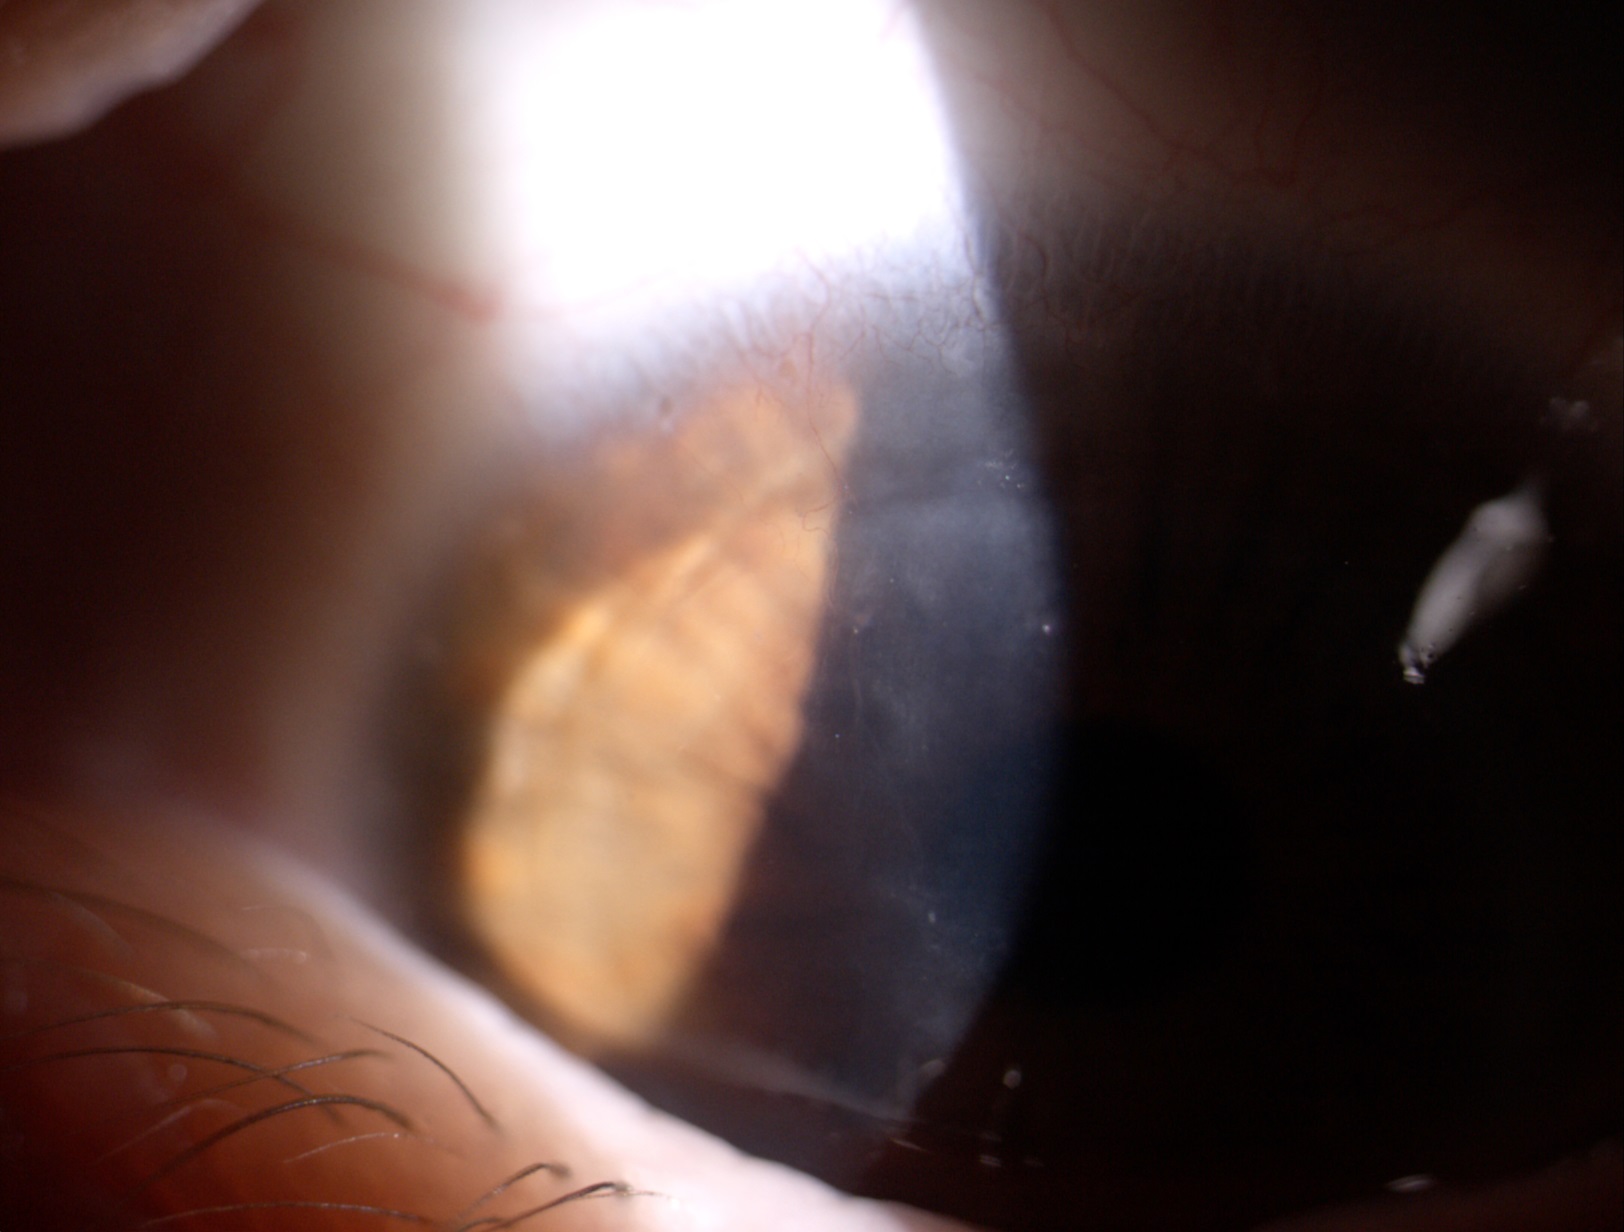

le invio immagini di [...]. Da controllo mensile direi che tutto procede per il meglio con uso di lac RGP su OS. per un massimo di 8 ore giornaliere.